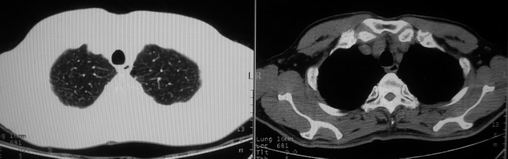

男,62岁,咳血两天。无其他不适。

右肺上叶浅淡密度增高影,考虑炎性病变

片状磨玻璃影,考虑肺泡出血可能性大,其他不排除,建议hrct

右上磨玻璃样密度影,考虑就是个肺泡出血,别的没有

病灶呈“磨玻璃影”,较薄,周围无卫星灶,很难一口说是肺结核,建议积极治疗后,短期复查!(支持考虑:肺泡出血!)

右肺上叶可见多发磨玻璃状影,符合肺泡内出血表现,严格意义上讲应该是肺泡内积血。引起出血的原因很多,不一定非得结核所致。